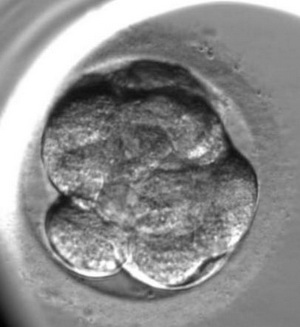

L’enregistrement du développement de l’embryon est le suivant :

Pour l’évaluation de la qualité des embryons on utilise la méthode d’analyse morphologique. Les embryons sont évalués selon les critères suivants : la quantité des blastomères, l’égalité des blastomères et la présence de fragmentation (des blastomères normaux qui ont été détruits). Cependant, cette méthode qui est la plus ancienne a ses inconvénients, elle est subjective (elle dépend de l’expérience et du niveau de l’embryologiste), un embryon est extrêmement variable durant son développement un embryon de mauvaise qualité de deux jours peut se transformer en un bel enfant en bonne santé. En ce moment, on utilise une nouvelle méthode d’évaluation de la qualité des embryons c’est l’embryoscopie. Son principe est le suivant : toutes les 10 ou 20 minutes on prend une photo de l’embryon en 7 couches, avec l’utilisation d’un programme informatique, on applique les images l’une sur l’autre pour en faire une video, c’est « le résumé » de chaque embryon. Avec l’utilisation d’un programme informatique spécifique, on mesure les paramètres clés du développement embryonnaire :